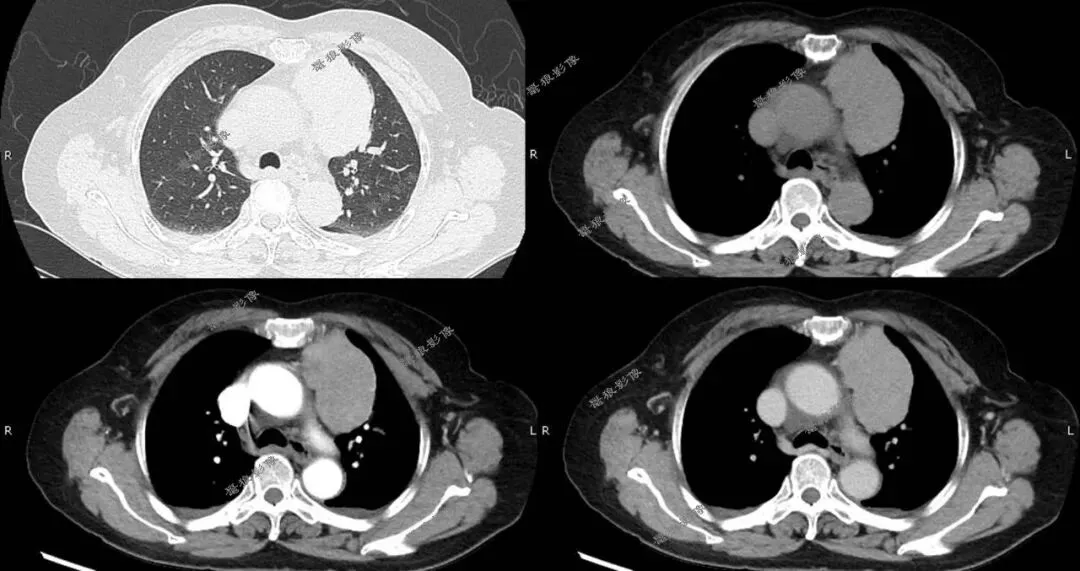

二、后行胸部CT平扫+增强(如下图):

胸部CT平扫+增强提示:

右肺下叶背段(IM118)见一浅分叶状实性结节,大小约为17mm×14mm,病灶边缘可见多发短毛刺,邻近斜裂稍凹陷,增强扫描病灶呈较明显不均匀强化。左前上纵隔见一类圆形软组织肿块,边界尚清,大小约69mm×44mm×51mm,密度较均匀,增强扫描病灶呈较均匀性轻度强化。

1.右肺下叶背段浅分叶状实性结节,考虑肺Ca可能性大,建议治疗后复查。

2.左前上纵隔软组织肿块,考虑胸腺瘤,必要时进一步检查以除外其它肿瘤性病变。